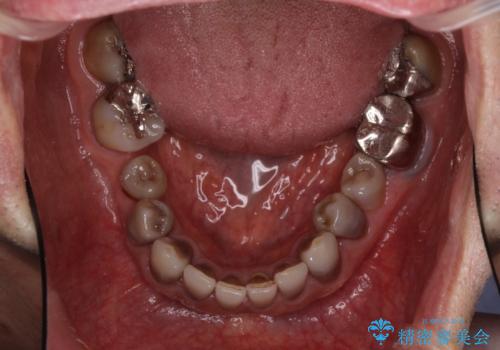

- 前歯のクロスバイトを気にして来院された患者様です。

骨格的に下顎が前方位ではありますが、歯並びが改善されれば正常咬合となることが分かったため、インビザラインを用いて咬み合わせを改善していくこととしました。